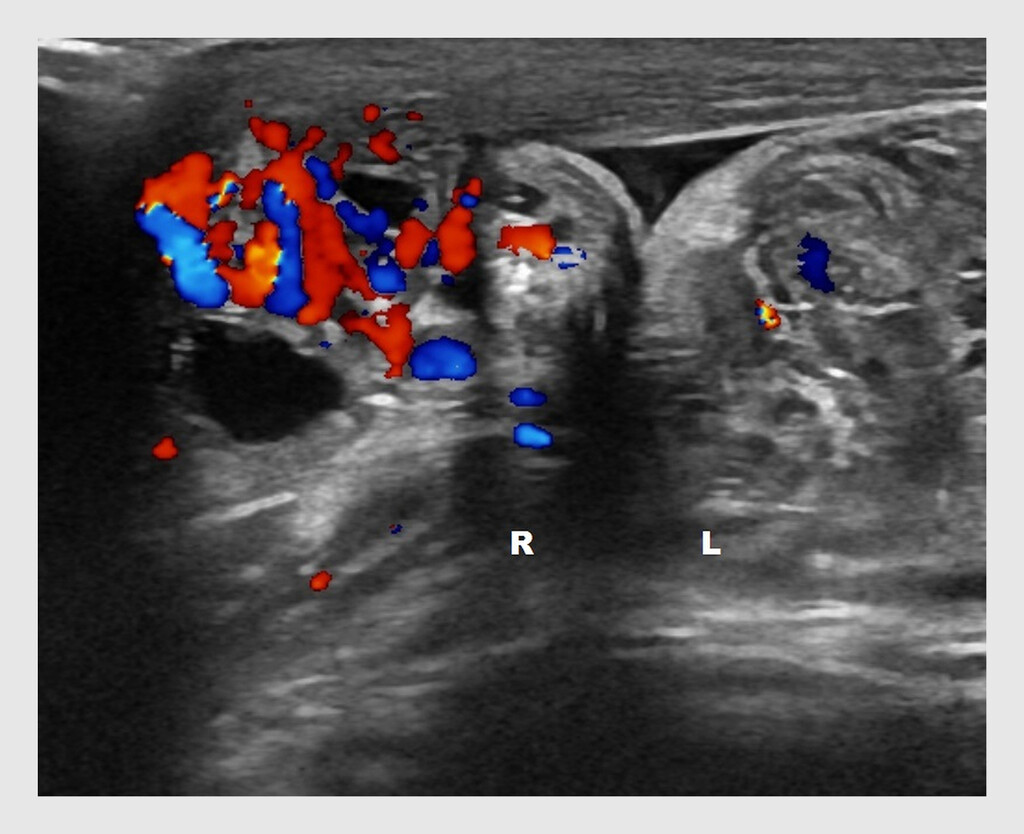

In deze klinische les beschrijven wij de casus van een gezonde, 16-jarige jongeman met een torsio testis die zeer kort na een doorgemaakte epididymitis ontstaat. Met deze les illustreren wij hoe belangrijk het is om de diagnose ‘epididymitis’ te heroverwegen bij patiënten bij wie het scrotum opnieuw pijnlijk wordt. Wanneer een torsio testis in een vroeg stadium wordt herkend en behandeld, is er een grotere kans op behoud van de testis en de fertiliteit.1,2

Patiënt, een gezonde, 16-jarige jongeman, komt op de Spoedeisende Hulp, omdat zijn rechter hemiscrotum sinds 2 dagen pijnlijk en gezwollen is. Hij gebruikt geen medicatie. Bij aankomst op de SEH geeft patiënt aan dat de pijn inmiddels is afgenomen, maar dat de zwelling persisteert. Hij heeft geen buikpijn gehad, is niet ziek geweest en heeft niet gebraakt. Ook heeft hij geen mictie- of defecatieklachten. Patiënt is niet seksueel actief.

Bij lichamelijk onderzoek zien wij een niet-zieke, adequate patiënt met een helder bewustzijn. Bij palpatie van de linker testis voelen wij een ronde, elastische, gladde en regelmatige testis; de epididymis kan goed worden onderscheiden van de testis. Patiënt geeft geen pijn aan tijdens het onderzoek van het linker hemiscrotum. Bij palpatie van de rechter testis voelen wij een elastische, onregelmatige zwelling; testis en epididymis zijn ditmaal niet goed van elkaar te onderscheiden. De rechter epididymis is gevoelig. Differentiaaldiagnostisch denken wij aan…

In deze klinische les wordt een tevoren gezonde, 16-jarige jongeman beschreven met een sedert twee dagen pijnlijk gezwollen rechter hemiscrotum. Gezien leeftijd en anamnese, was de diagnose torsio testis wel zeer waarschijnlijk. Omdat de pijn afgezakt was, was er waarschijnlijk sprake van òf necrose òf een detorsie. Gezien de beschreven goede doorbloeding van de rechter testis en epididymis bij echografie, was er vermoedelijk sprake van een status na detorsie. Het ontbreken van de cruciale echografische afbeelding  van deze rechter testis, maakt deze klinische les niet echt sterker. De radioloog heeft vermoedelijk zuiver op het echografisch beeld gevaren, en kliniek en leeftijd onvoldoende betrokken in zijn conclusie, vandaar de onjuiste diagnose van epididymitis. De clinicus heeft deze diagnose helaas overgenomen, en de patiënt is met pijnstillers naar huis gestuurd. Zes dagen later is er vermoedelijk weer een torsio opgetreden die uiteindelijk twee dagen later echografisch en later bij operatie bevestigd werd, de testis was toen niet meer te redden. De lezer blijft in verwarring achter als de auteurs aan het eind concluderen dat er sprake moet zijn geweest van een nieuw ontstane torsio testis in het verloop van een acute  epididymitis. Eens te meer geldt: “Eine Krankheit genügt”